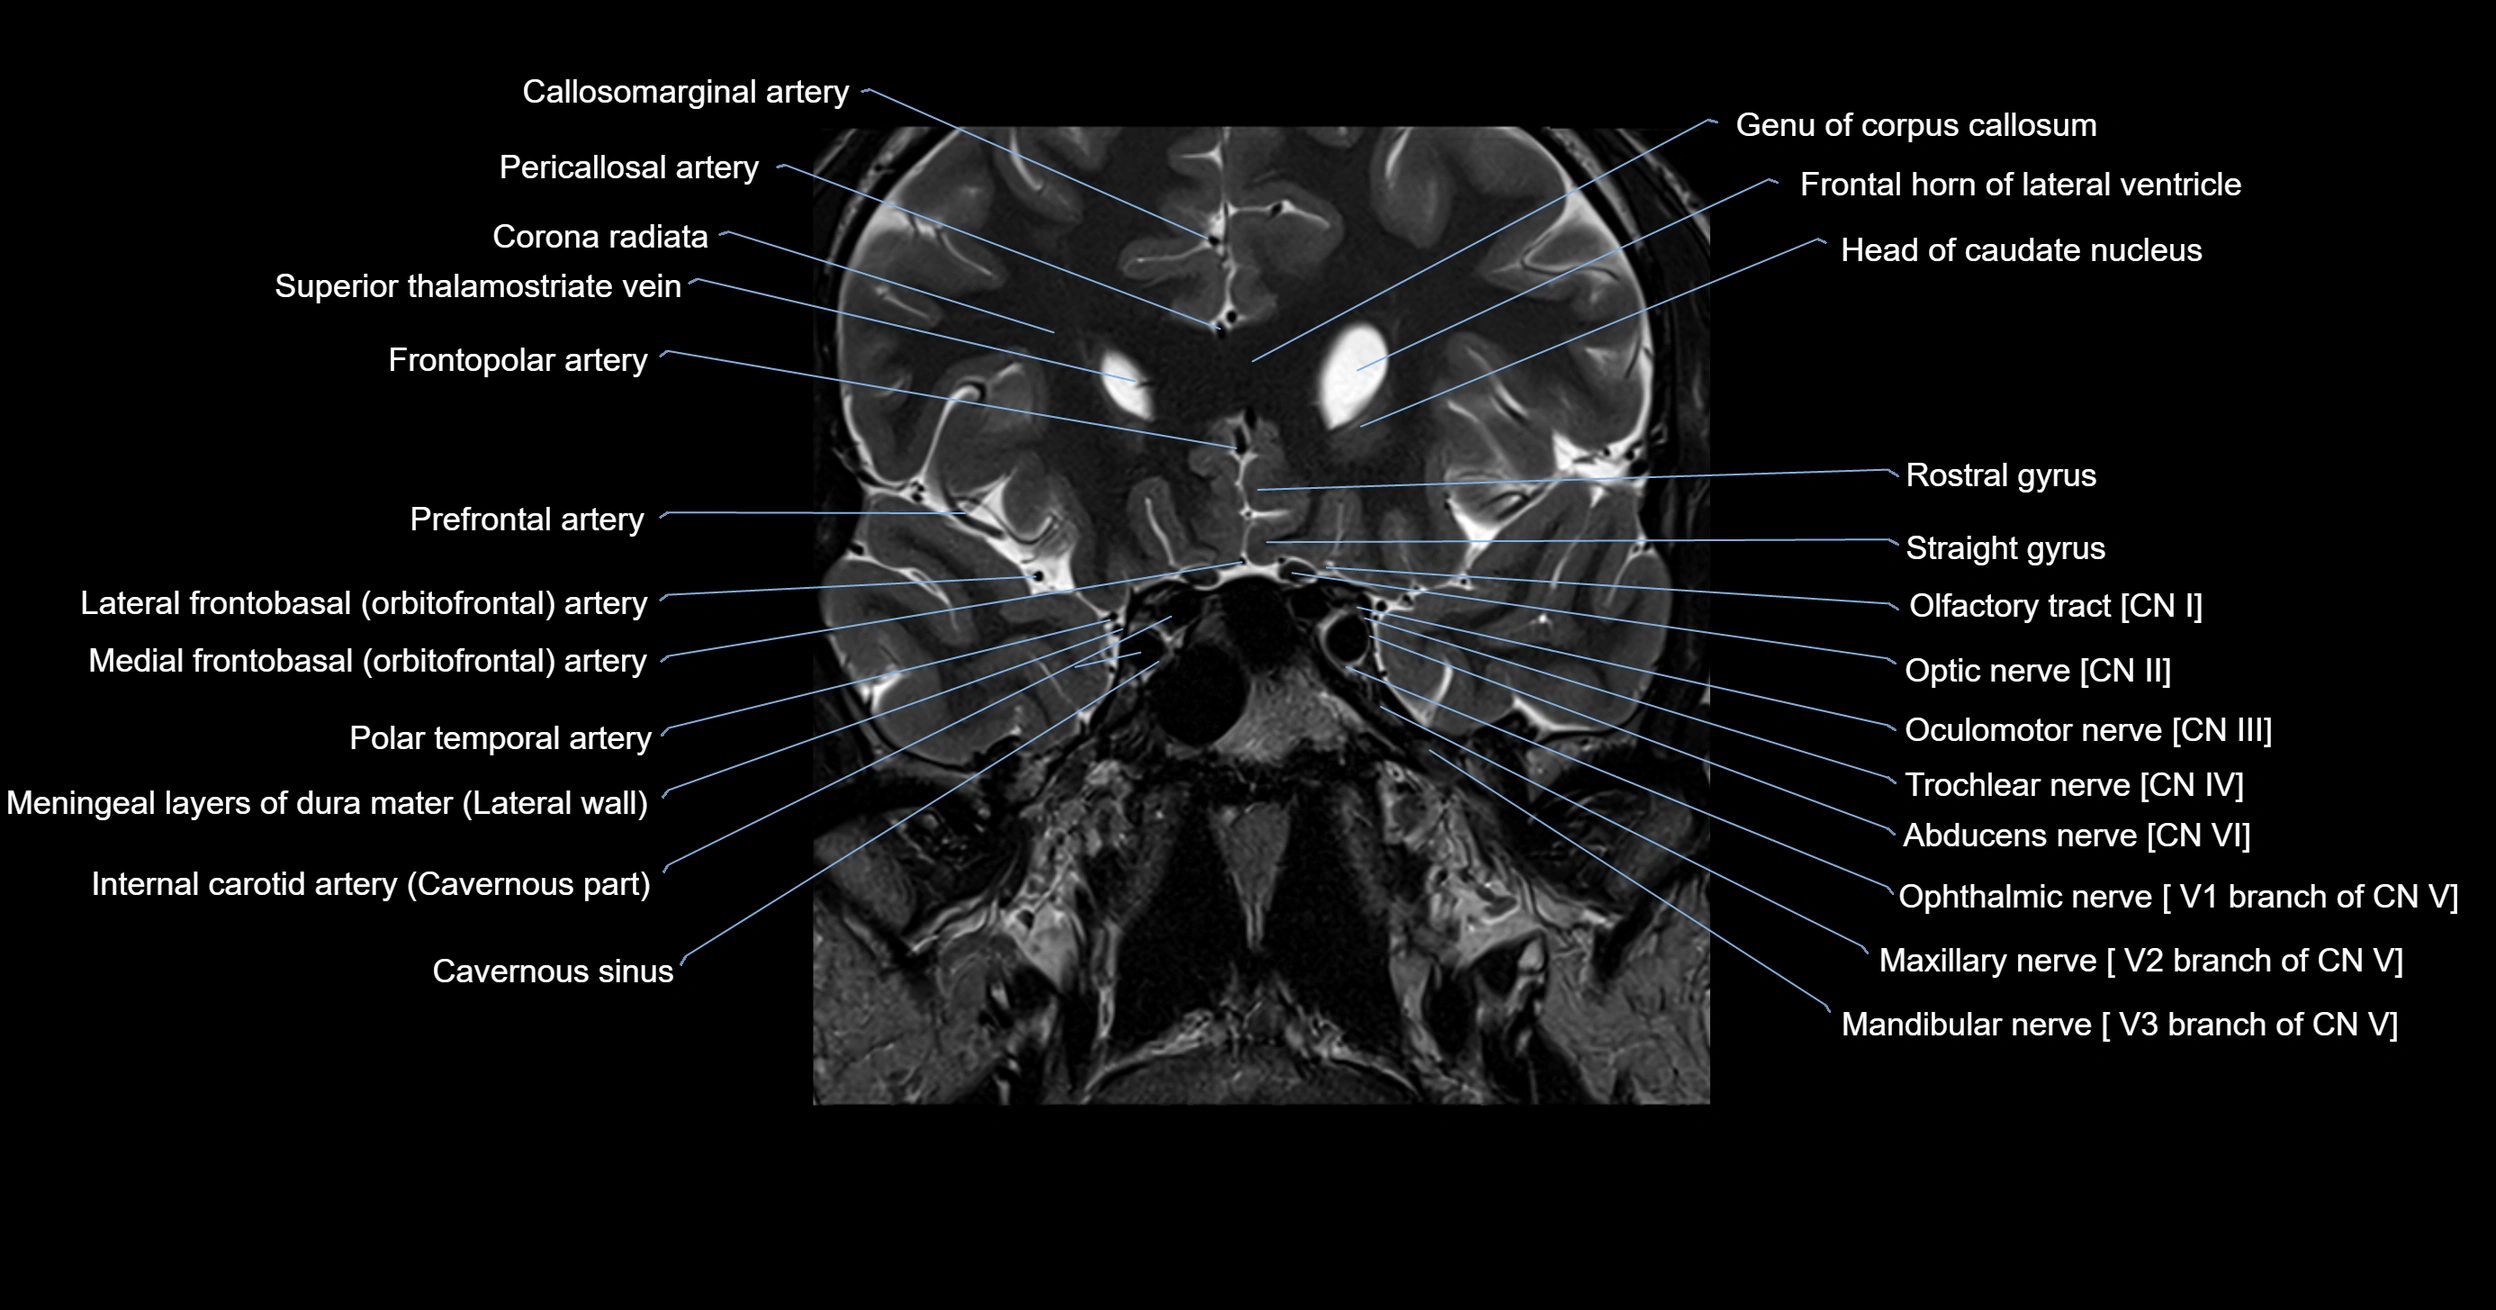

MRI images